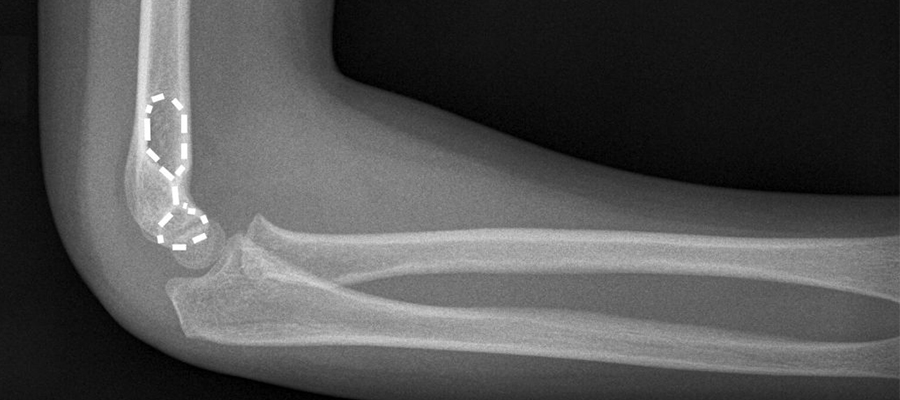

الكسور والخلع في المرفق..

يحدث نتيجة السقوط على اليد أو المرفق. في حالة وجود خلع فقط دون كسر ، يتم تثبيت خلع تحت التخدير ويتم إجراء التث..